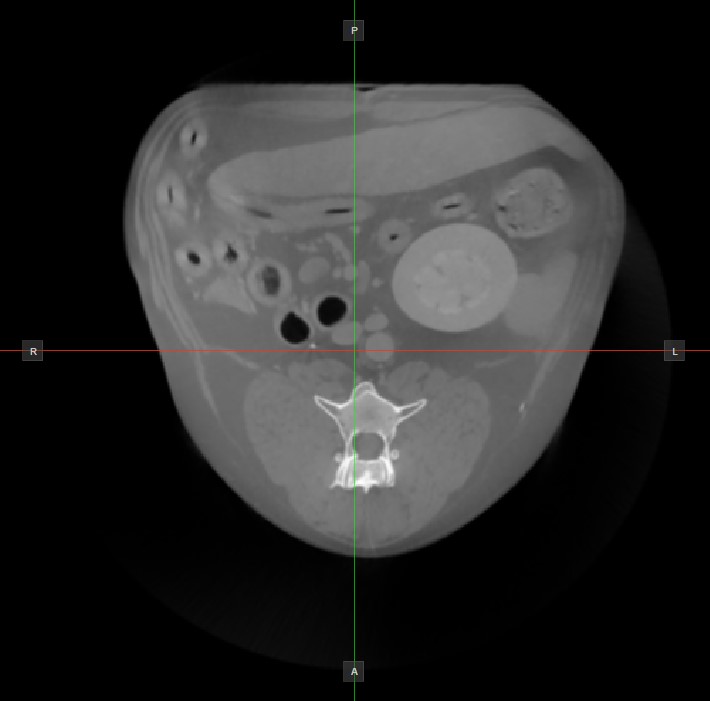

The position and intersection of the other two image planes not represented in the active viewport is indicated by two vertical and horizontal lines called slicers. The endpoints of each slicer are labeled with a letter that corresponds to the appropriate direction/side of the 3D volume, based on the RAS coordinate system.

Only four sides of the available six are indicated on each 2D viewport. The labels and the corresponding side are the following:

Patient Right (R), indicating the right side of the body

Patient Left (L), indicating the left side of the body

Anterior (A), indicating the front side of the body

Posterior (P), indicating the back side of the body

Superior (S), indicating the top side of the body

Inferior (I), indicating the bottom side of the body